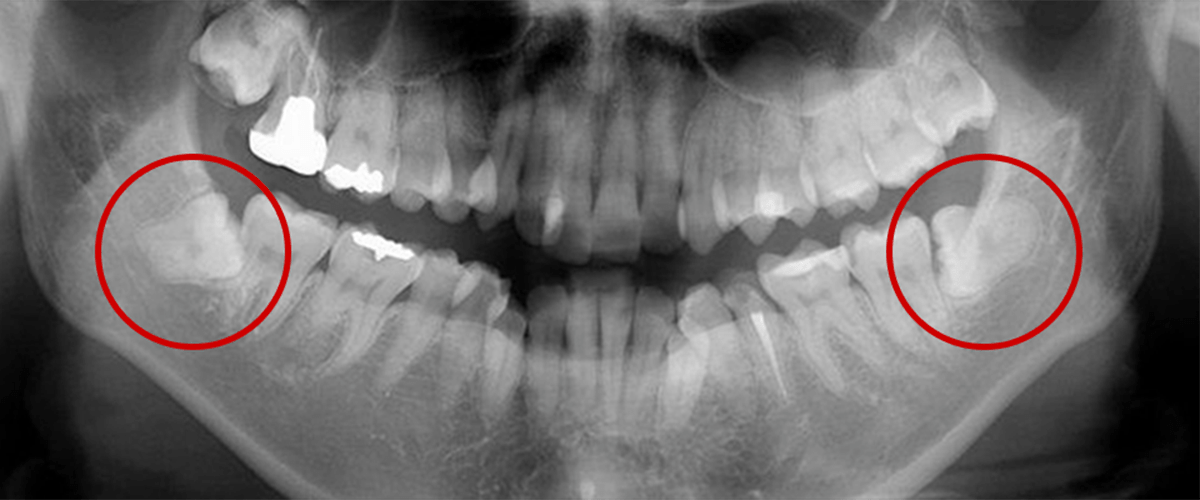

親知らずとは、大臼歯(大人の奥歯)の中で一番後ろに位置する第3大臼歯

智歯とも呼ばれ、20歳前後で生えてくることが多く、個人差があります。

歯ぐきに埋まったまま生えないことや生まれつき親知らずが存在しない場合もあります。

親知らずが横や斜めに生えてきたり、歯ぐきがかぶっていることがあります。そのため、親知らずの周囲には細菌が残りやすく、以下のようなトラブルを起こし、痛みの原因になります。

- 歯が押されて歯並びが変わってしまう

- 第2大臼歯が親知らずのために、むし歯や歯周病が進行している場合や、将来的にそのリスクが高い場合

- 第2大臼歯の歯の根に、親知らずが当たっている